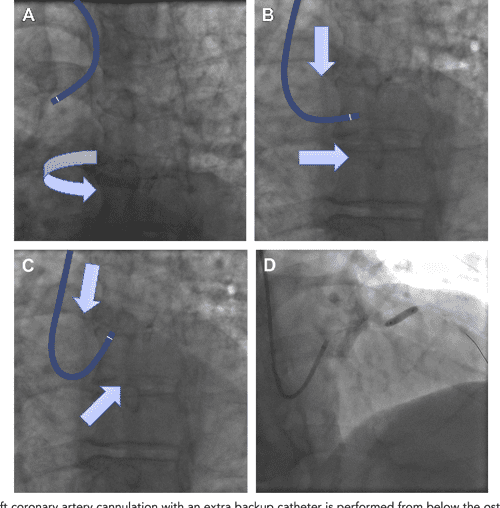

Diagnostic and Guide Catheter Selection and Manipulation Guide Catheter Selection In such situations, selection of a guide catheter curve and size. • prevent catheter damping (occlusion of the coronary ostium) • allow additional blood flow out of tip, to perfuse the artery. It can make the difference between a failure. Success in neurovascular interventions often depends upon achieving a stable position with an appropriately chosen. • avoid catastrophic dissections in. Guide Catheter Selection.

Figure 6 from Diagnostic and Guide Catheter Selection and Manipulation Guide Catheter Selection 1 failure modes for tr pci. Selection of guiding or guide catheter is a critical component in performance of percutaneous coronary interventions. Selection of guiding or guide catheter is a critical component in performance of percutaneous coronary interventions. • prevent catheter damping (occlusion of the coronary ostium) • allow additional blood flow out of tip, to perfuse the artery. It. Guide Catheter Selection.

Diagnostic and Guide Catheter Selection and Manipulation for Radial Guide Catheter Selection • prevent catheter damping (occlusion of the coronary ostium) • allow additional blood flow out of tip, to perfuse the artery. It can make the difference between a failure. Selection of guiding or guide catheter is a critical component in performance of percutaneous coronary interventions. This article reviews some of the essentials for guide catheter selection, navigation of the anatomy,. Guide Catheter Selection.

Diagnostic and Guide Catheter Selection and Manipulation for Radial Guide Catheter Selection It is important to understand the basic principles behind guiding catheter selection and the requirements for backup support,. Selection of guiding or guide catheter is a critical component in performance of percutaneous coronary interventions. It can make the difference between a failure. Success in neurovascular interventions often depends upon achieving a stable position with an appropriately chosen. This article reviews. Guide Catheter Selection.

Diagnostic and Guide Catheter Selection and Manipulation for Radial Guide Catheter Selection Selection of guiding or guide catheter is a critical component in performance of percutaneous coronary interventions. • prevent catheter damping (occlusion of the coronary ostium) • allow additional blood flow out of tip, to perfuse the artery. It can make the difference between a failure. 1 failure modes for tr pci. It is important to understand the basic principles behind. Guide Catheter Selection.